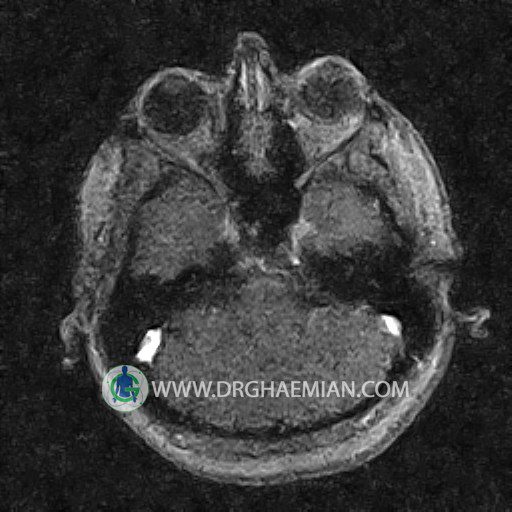

ام آر وی یک روش تصویربرداری دقیق و غیر تهاجمی است که برای معاینه ورید های بدن و ارزیابی سلامت رگ ها استفاده می شود. ورید ها خون را از اعضای بدن به قلب باز می گرداند تا دوباره اکسیژن و مواد مغذی به خون داده شود. ام آر وی جریان خون را ارزیابی و موارد غیرعادی مضر مانند لخته های خونی را شناسایی می کند. در این کیس ترومبوز دیواری مغز در سینوس عرضی راست و ترمبوز جزئی در سینوس عرضی چپ دیده می شود.

The great cerebral vein Galen inferior sagittal , straight sinus and left sigmoid sinus appear normal.

The right sigmoid sinus present a normal caliber.

The other evaluable deep cerebral veins , basal and labbe are normally developed and patent.

The other evaluable portions of the neurocranium show no abnormalities.